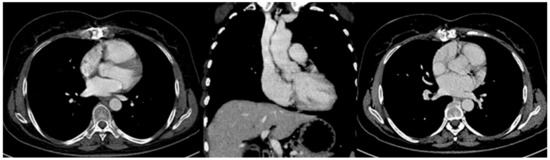

Clinical or Imaging Diagnosis of the Current Medical Practice for Superior Vena Cava Syndrome?

Most cases of superior vena cava syndrome are easily diagnosed bya clinical examination alone, but several diagnostic tests and procedures can be helpful. When a patient presentswith a suspected diagnosis of superior vena cava syndrome, the first step is to obtain an imaging [...] Read more.

Most cases of superior vena cava syndrome are easily diagnosed bya clinical examination alone, but several diagnostic tests and procedures can be helpful. When a patient presentswith a suspected diagnosis of superior vena cava syndrome, the first step is to obtain an imaging study that confirms the diagnosis and aids treatment decisions. Magnetic resonance imaging, contrast-enhanced CT scanning, radionuclide flow studies and traditional venography are all appropriate techniques. Still, the CT scan is the most readily available technology in most centers. The CT scan and magnetic resonance imaging also provide information on possible etiologies and can therefore direct the approach towards a tissue diagnosis. Full article